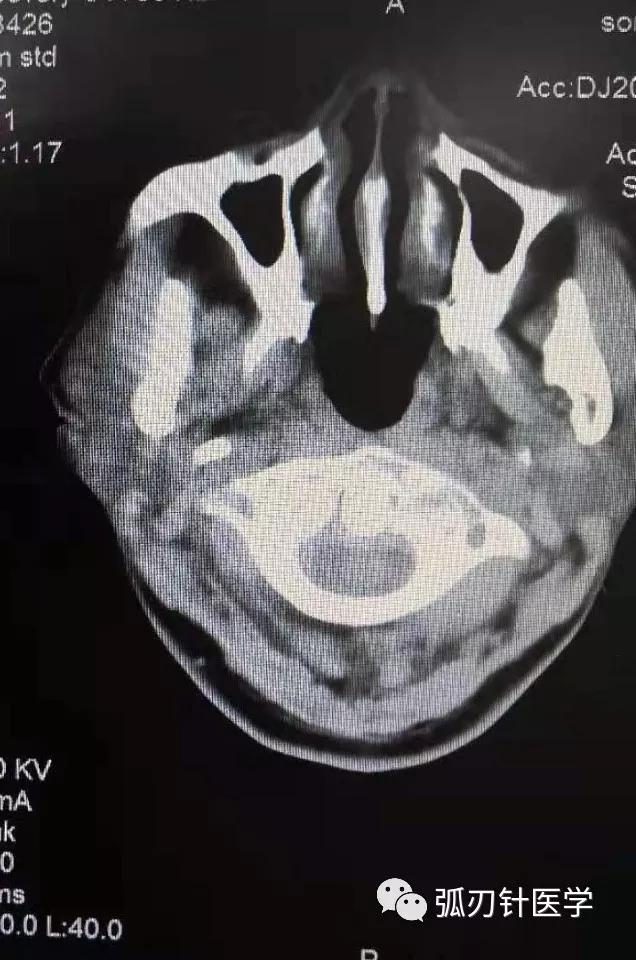

最后,还有个问题,我一直不明白:就是环枢椎错位,在张口位X线片时,左宽右窄,应该处理宽的那一侧,还是说处理窄的那一侧?我是使用触诊的方法进行处理,不知道正确与否,还请王老师指点迷津。总之,这次收获很多,再次感谢老师的精彩讲解。

环枢椎错位,齿状突不居中,有生理性的,也有病理性的,很多情况皆可导致。

究竟处理哪一侧?

影像检查只是辅助,灶点在哪里就处理哪里,触诊寻找灶点才是弧刃针治疗本病的关键。